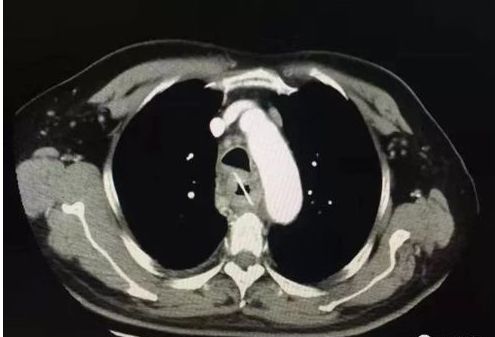

进镜见喉炎,食管下段糜烂,食管距门齿20~35cm可见菜花状隆起,表面糜烂粗糙,覆厚白苔污秽苔,占据管腔1/3,内镜顺利通过,触之易出血,活检,质地脆,弹性差。作为消化内科的医生,几乎没有疑问,这就是食管癌,而且是晚期,临床表现。返病房,待病理。两天后病理检查的结果出来了:“食管”鳞状上皮黏膜慢性炎局部急性炎及上皮增生。这下子矛盾来了,这眼看着的食管癌,可是病理却连个不典型增生都没有发现,开刀?放疗?化疗?没有病理证实是万万不可能的!决定复查螺旋CT想了解食管病变壁外的情况。结果如下:

显示:食管异物!决定行胃镜再次检查,进镜见:食管上段竟然横挂着一根弯弯的骨头!这可不能随便取!万一骨头扎进了主动脉,贸然取出会当场大出血死人的!

因为已经做了胸部螺旋CT,联系放射科,经过仔细寻找,在食管的部位发现了骨头,虽然已经刺破食管,有了穿孔,万幸的却是骨头并没有在主动脉内,通过胃镜把这个骨头取了出来!